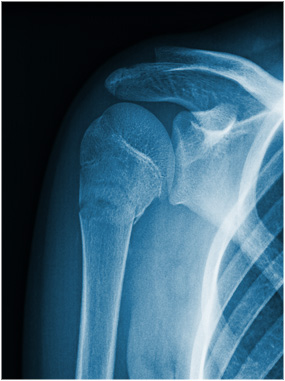

Röntgendiagnostik

Zur präzisen Diagnostik von Verletzungen und Erkrankungen am Skelett ist die Röntgendiagnostik auch heute noch unverzichtbar.

Wir verfügen über eine hochmoderne digitale Röntgenanlage und speziell geschulte Mitarbeiterinnen, die die Röntgenuntersuchung durchführen. Direkt im Anschluss werden die Bilder vom Arzt befundet und Ihnen erklärt.